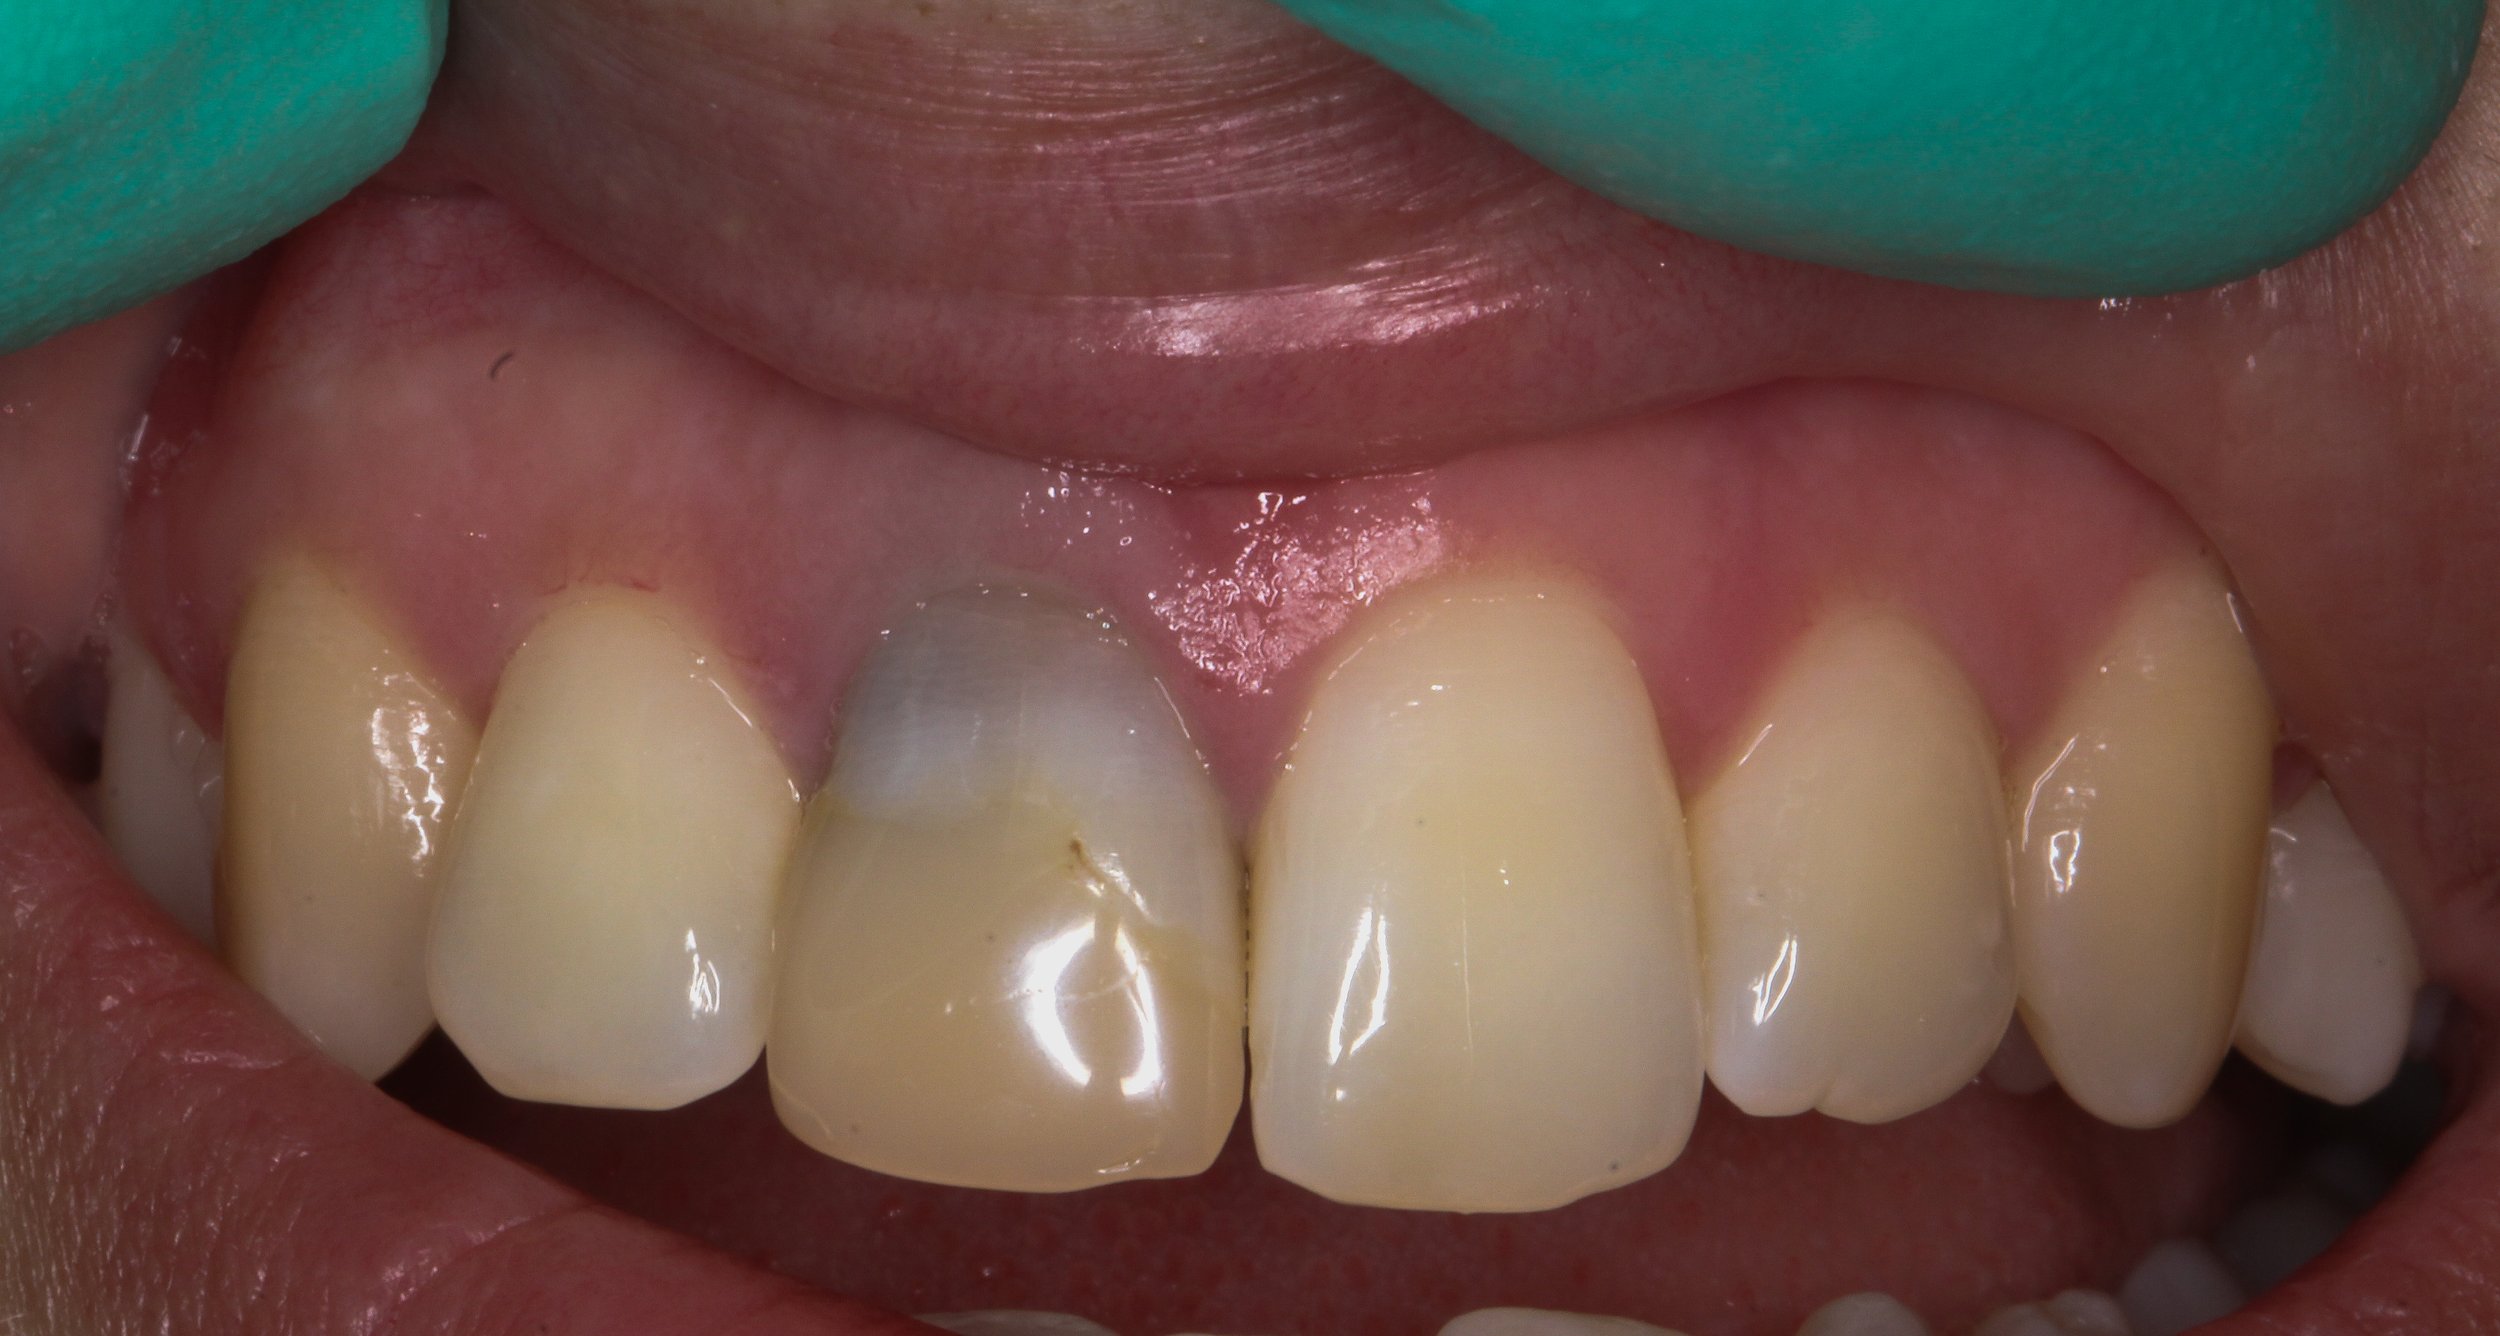

Fixed pros